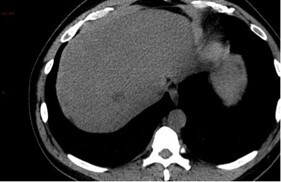

Finalement, après réinjection de produit de contraste, le scanner suivant est réalisé.

Question 15 - Quelle est votre première hypothèse diagnostique ?

Le diagnostic d’œdème aigu du poumon (OAP) se fait sur un faisceau d’arguments : la cardiomégalie avec dilatation des veines pulmonaires, les plages en verre dépoli et d’épaississement des septa interlobulaires déclives respectant les lobes supérieurs, ainsi que les épanchements pleuraux bilatéraux d’abondance modérée. L’accumulation de ces éléments rend le diagnostic d’OAP le plus probable.

Il n’y pas de défect endoluminal des artères pulmonaires permettant d’éliminer l’embolie pulmonaire. Il n’y a pas non plus de signe indirect d’embolie pulmonaire (infarctus pulmonaire).

L’hémorragie intra-alvéolaire peut aussi se manifester sous la forme de plages de verre dépoli, mais le contexte est différent, et la cardiomégalie avec dilatation des veines pulmonaires ne sont pas en faveur.

L’absence de condensation parenchymateuse et la topographie des anomalies parenchymateuses pulmonaires n’est pas en faveur d’une pneumopathie bilatérale.